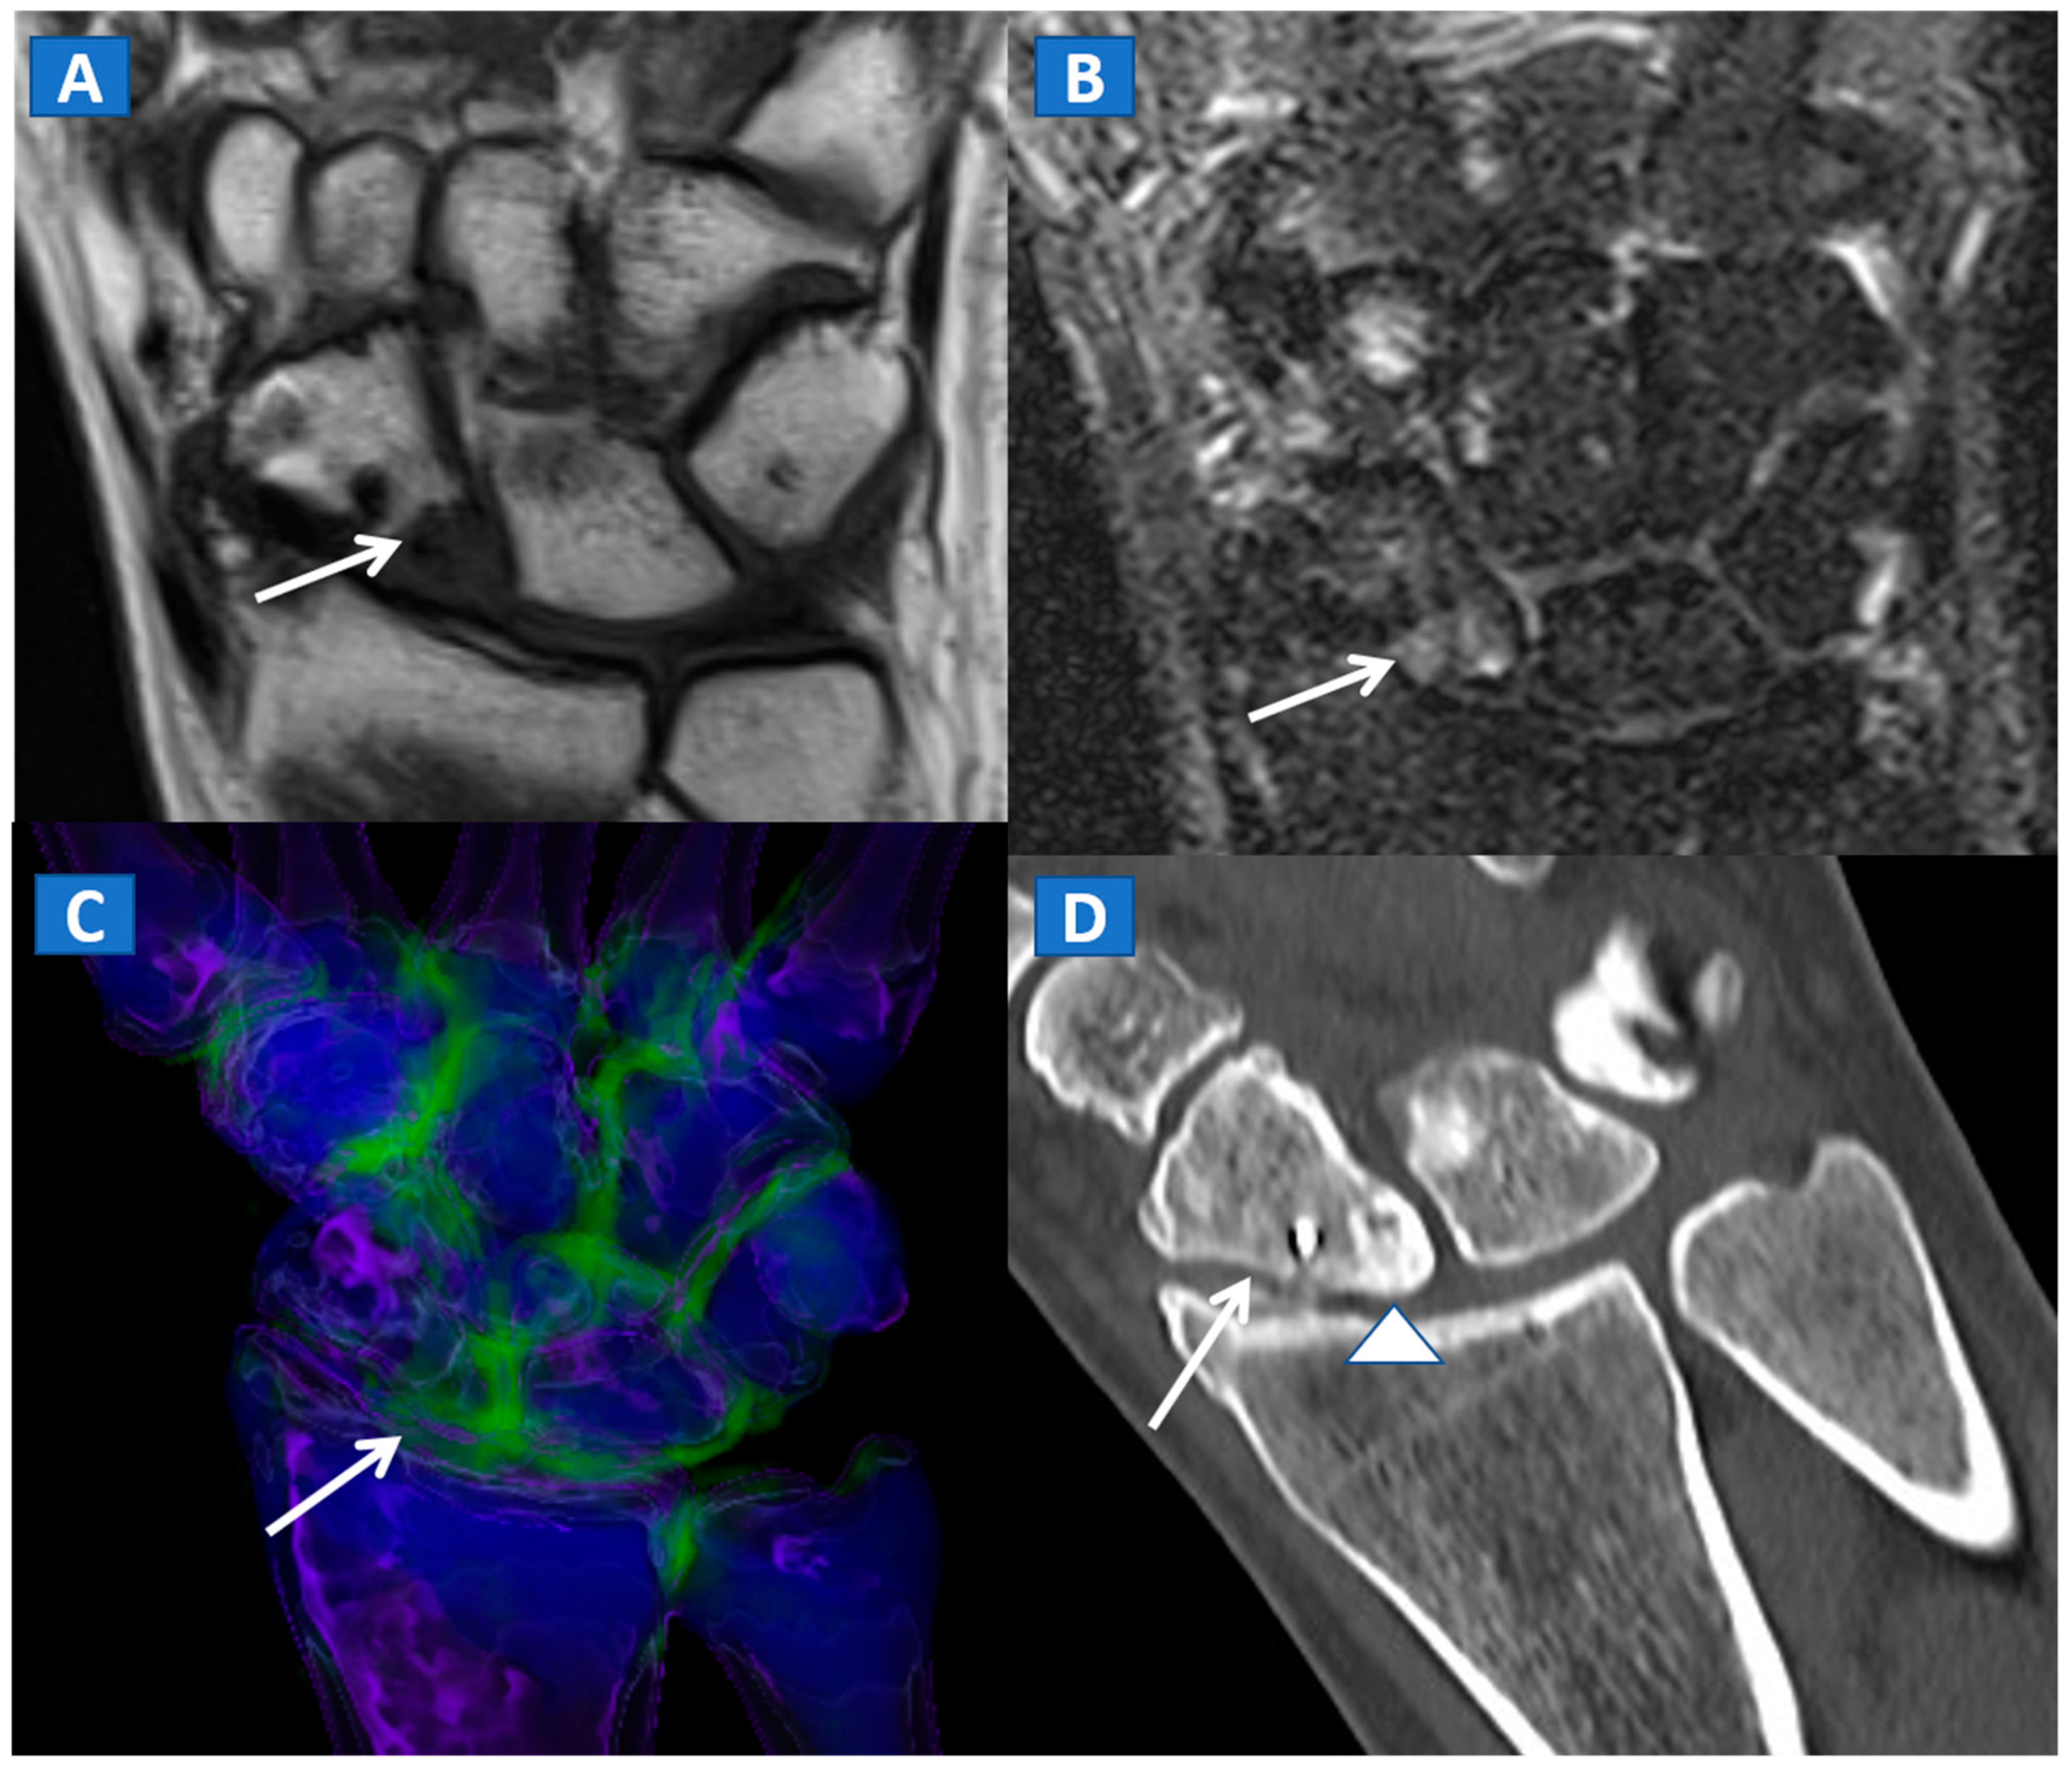

Figure 1.

A 43-year-old male with low back pain following high-energy trauma, with no vertebral fractures. On the sagittal STIR MRI image (A), all lumbar vertebral bodies show a normal shape and signal intensity. On the 3D DECT image, on the para-sagittal plane (B), normal vertebral bodies are coded in blue, whereas density increases, due to increased water content, are coded in green. As expected, the normal intervertebral discs are coded in green. In addition, normal cortical bone is also coded in green, due to an incomplete subtraction process. On the corresponding 1 mm sagittal 2D DECT image (C) there is a color lookup table that codes bone marrow and areas of oedema in shades of green-yellow to orange-red. DE-specific information has been fused with conventional grayscale morphological images (thickness, 1 mm; increment, 1 mm). The range of densities is set between −150 and 100 HU, with underlying normal bone visualized without any superimposition for density values below the −50 HU cut-off.

Figure 2.

A 62-year-old female with traumatic low back pain following a fall. On the sagittal standard 1 mm CT image (A) it is not possible to identify the fresh fracture. On the coronal 3D DECT image (B), BME of the L1 vertebral body is coded in green (thick arrow), with some mild oedema depicted on the L2 superior endplate (thin arrow). On the sagittal STIR MRI image (C), a fresh fracture of the L1 body is confirmed, with mild oedema located close to the superior endplate (thick arrow). There is no BME of the L2 body apparent on the STIR MRI image. On the corresponding 2D DECT image (D), the maximum level of superimposition of color-coded maps was used to confirm the presence of mild oedema on the L1 vertebral body (thick arrow) and to rule out the presence of significant oedema on the L2 body (thin arrow), thus avoiding a false positive finding.

DECT 3D images are usually evaluated first, coding BME in shades of green and coding normal bone in blue (Figure 1). These images serve to provide a clear visual overview of the whole anatomical area, prior to any focus on specific findings. 3D images are usually more sensitive for depicting BME than 2D images (Figure 2). 2D images are analyzed by super-imposing the DE-specific information onto conventional grayscale morphological images (thickness, 1 mm; increment, 1 mm). Usually, a color lookup table is applied, which codes BME in shades ranging from green-yellow to orange-red (Figure 1C), with a range of densities set between −150 and 100 HU (Figure 1C). Superimposed color-coded maps are utilized only when density values are above the −50 HU cut-off. This approach can be useful in distinguishing between severe and mild BME (Figure 2). Additional windowing can also be carried out by increasing or decreasing the level of super-imposition of color-coded images in order to confirm or rule out subtler findings (Figure 2).